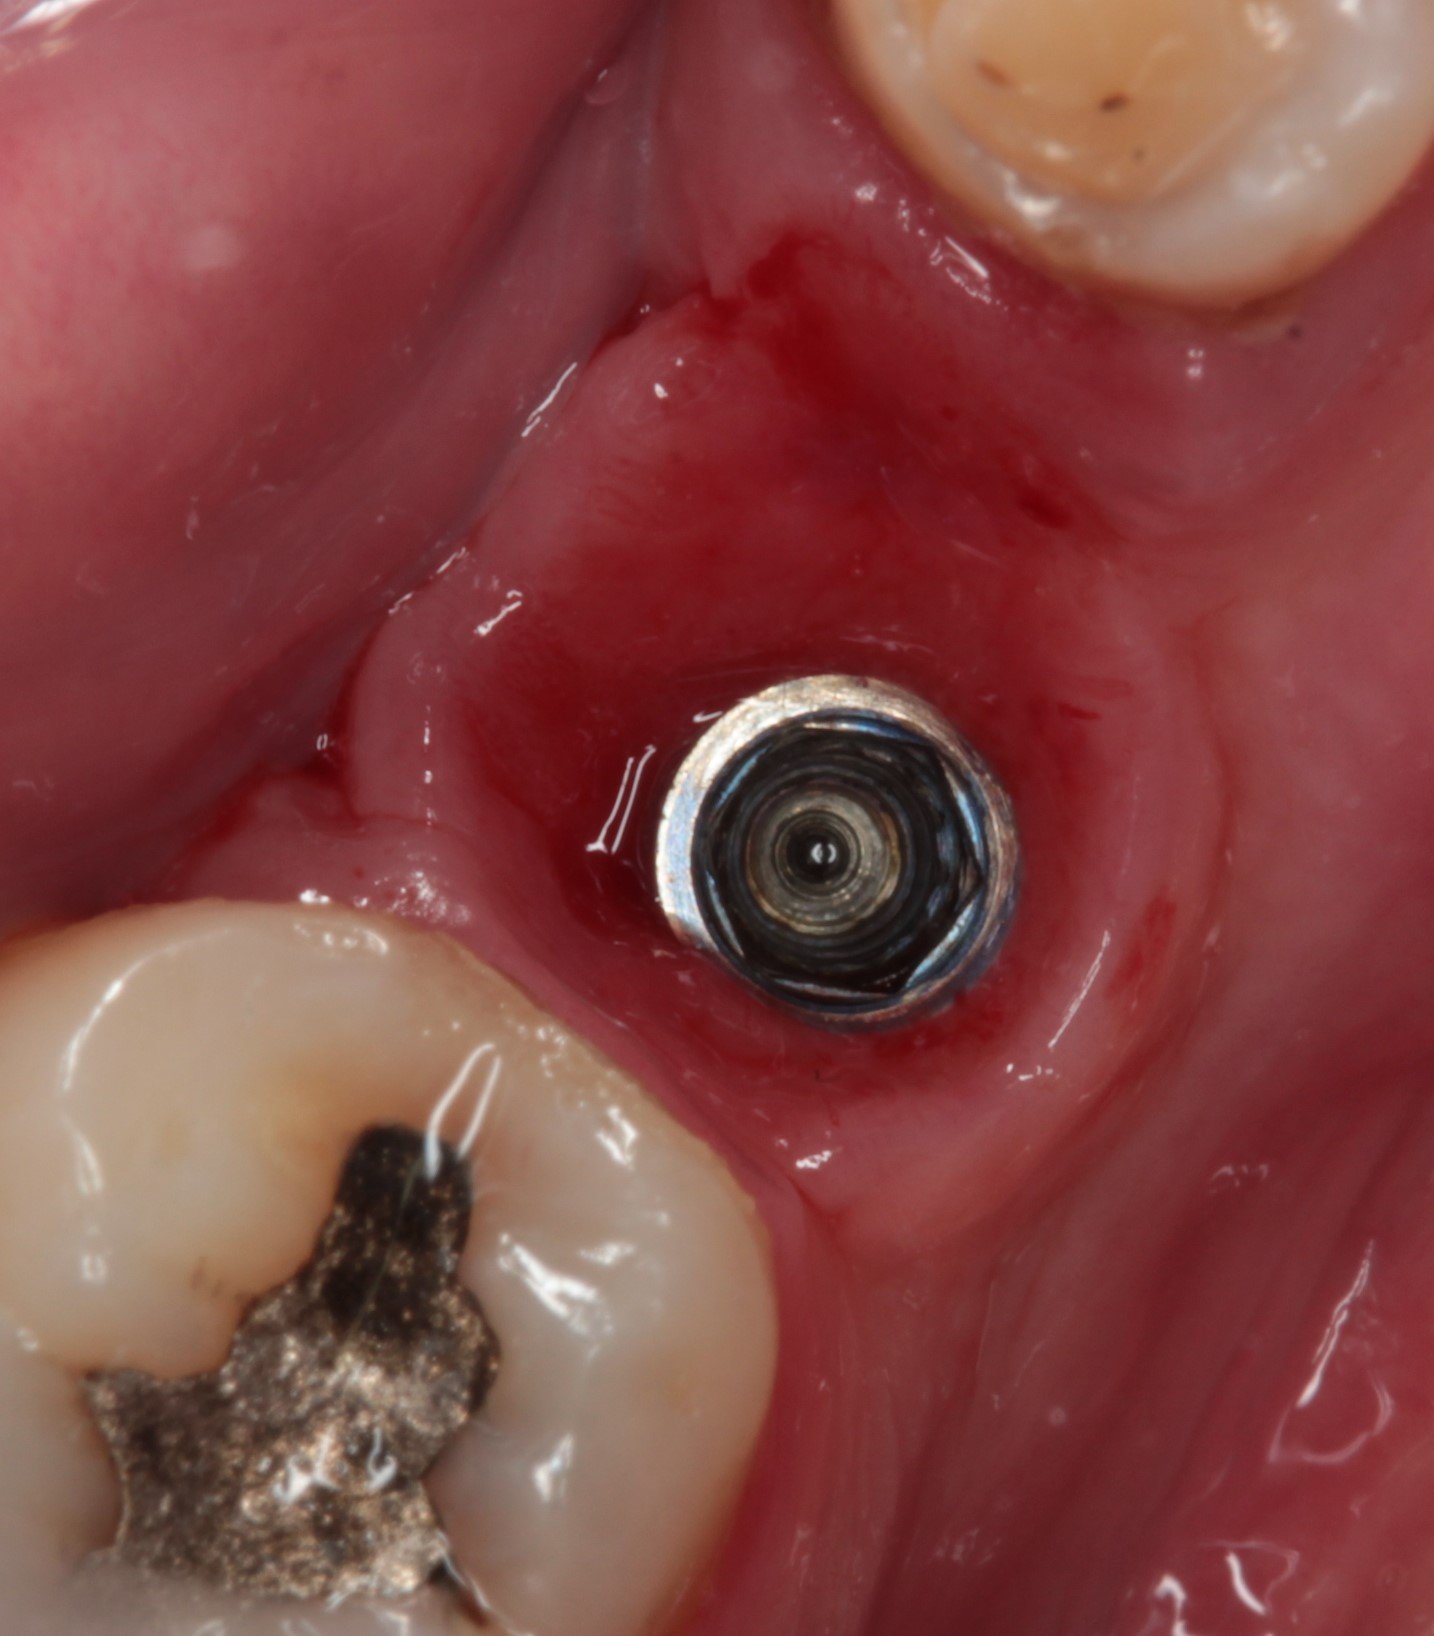

Que implante es el 36?

Buenas tardes compañeros. Acudo a vosotros para ver si me podéis ayudar. Sabríais decirme marca y modelo? Gracias!